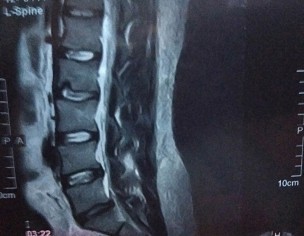

On 30nth April I was suffering from sever back and leg pain, after a day the pain was gone by taking some pain killers.. but day after tomorrow my thighs heel became numb .. And after MRI of lumbar sacral region and as per neurosurgeon Diogenes I have an problem in l5 s1 which disc is suggested me a surgery in first visit.. and a injection called epidural steroid injection ... I am scared from surgery and from this injection by reading of its risks from different internet channels ...